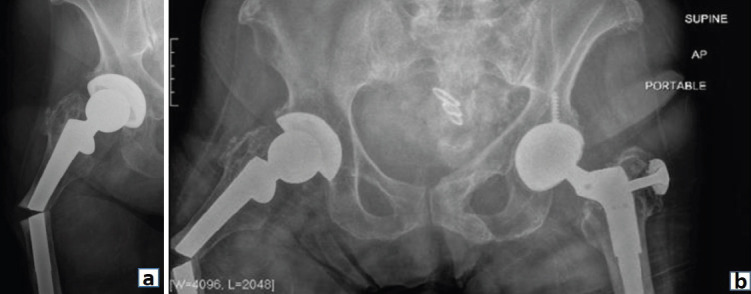

Case report: An 88-year-old female with multiple comorbidities, including osteoporosis and a history of bisphosphonate therapy, presented with an APFF of the right femur following a ground-level fall. One year prior, she had undergone uncomplicated THA with a long cylindrical, fully porous-coated femoral stem. Radiographs revealed a transverse fracture at the subtrochanteric region, lateral cortical thickening, and femoral stem breakage. Given the patient's medical history and the complexity of the fracture, revision surgery was indicated. Surgical intervention included the preservation of the proximal femoral stem and the removal of the distal stem segment, combined with periprosthetic plate fixation and cortical strut allograft for stabilization.

Conclusion: This case highlights the importance of individualized surgical planning in the management of APFFs, particularly those involving stem breakage. By preserving the proximal stem, a less invasive approach was achieved, minimizing surgical morbidity and supporting optimal fracture healing. The case underscores the potential benefit of preserving the femoral stem when appropriate, a strategy not widely explored in current literature. The findings contribute to the ongoing discussion of surgical options for APFFs and offer valuable guidance for future treatment approaches, especially as THA and bisphosphonate use continue to rise.